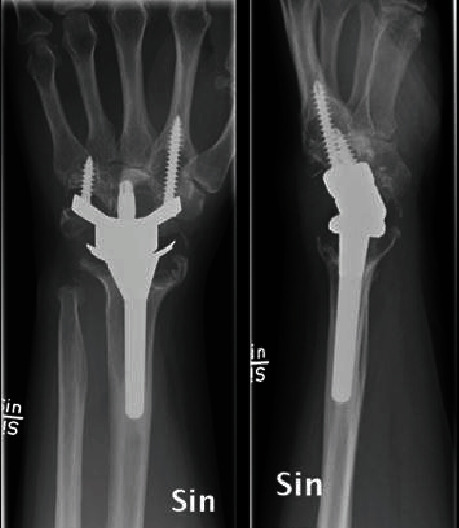

Metallosis is a known complication of arthroplasty and has been reported for the hip, knee, and shoulder joints. Metallosis pseudotumors have been linked to an increased risk of implant failure. We report a case of pseudotumor with massive bone loss following total wrist arthroplasty (TWA) using the Maestro implant. Revision to arthrodesis is possible, but issues with bone loss have to be addressed. We recommend caution in offering TWA to young patients with high functional demands.

已知金属沉积症是关节成形术的一种并发症,髋关节、膝关节和肩关节均有报道。金属病假瘤与植入失败的风险增加有关。我们报告了一例使用Maestro假体进行全腕关节置换术(TWA)后出现大量骨质流失的假瘤病例。翻修为关节置换术是可能的,但必须解决骨质流失的问题。我们建议对功能要求较高的年轻患者慎用 TWA。